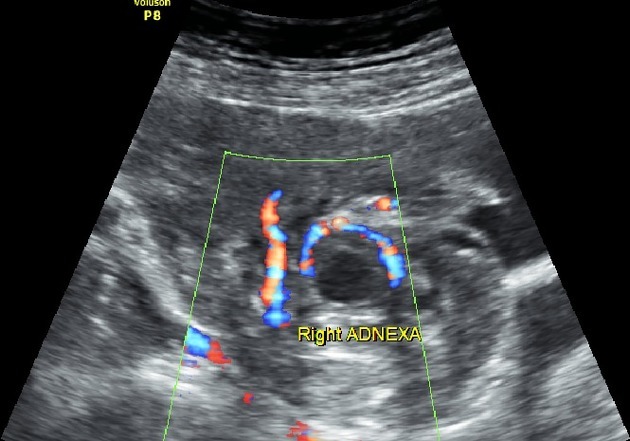

Tubal ring of fire sign

“Ring of fire” flow seen in the adenxa on ultrasound

Highly suspicious for ectopic pregnancy